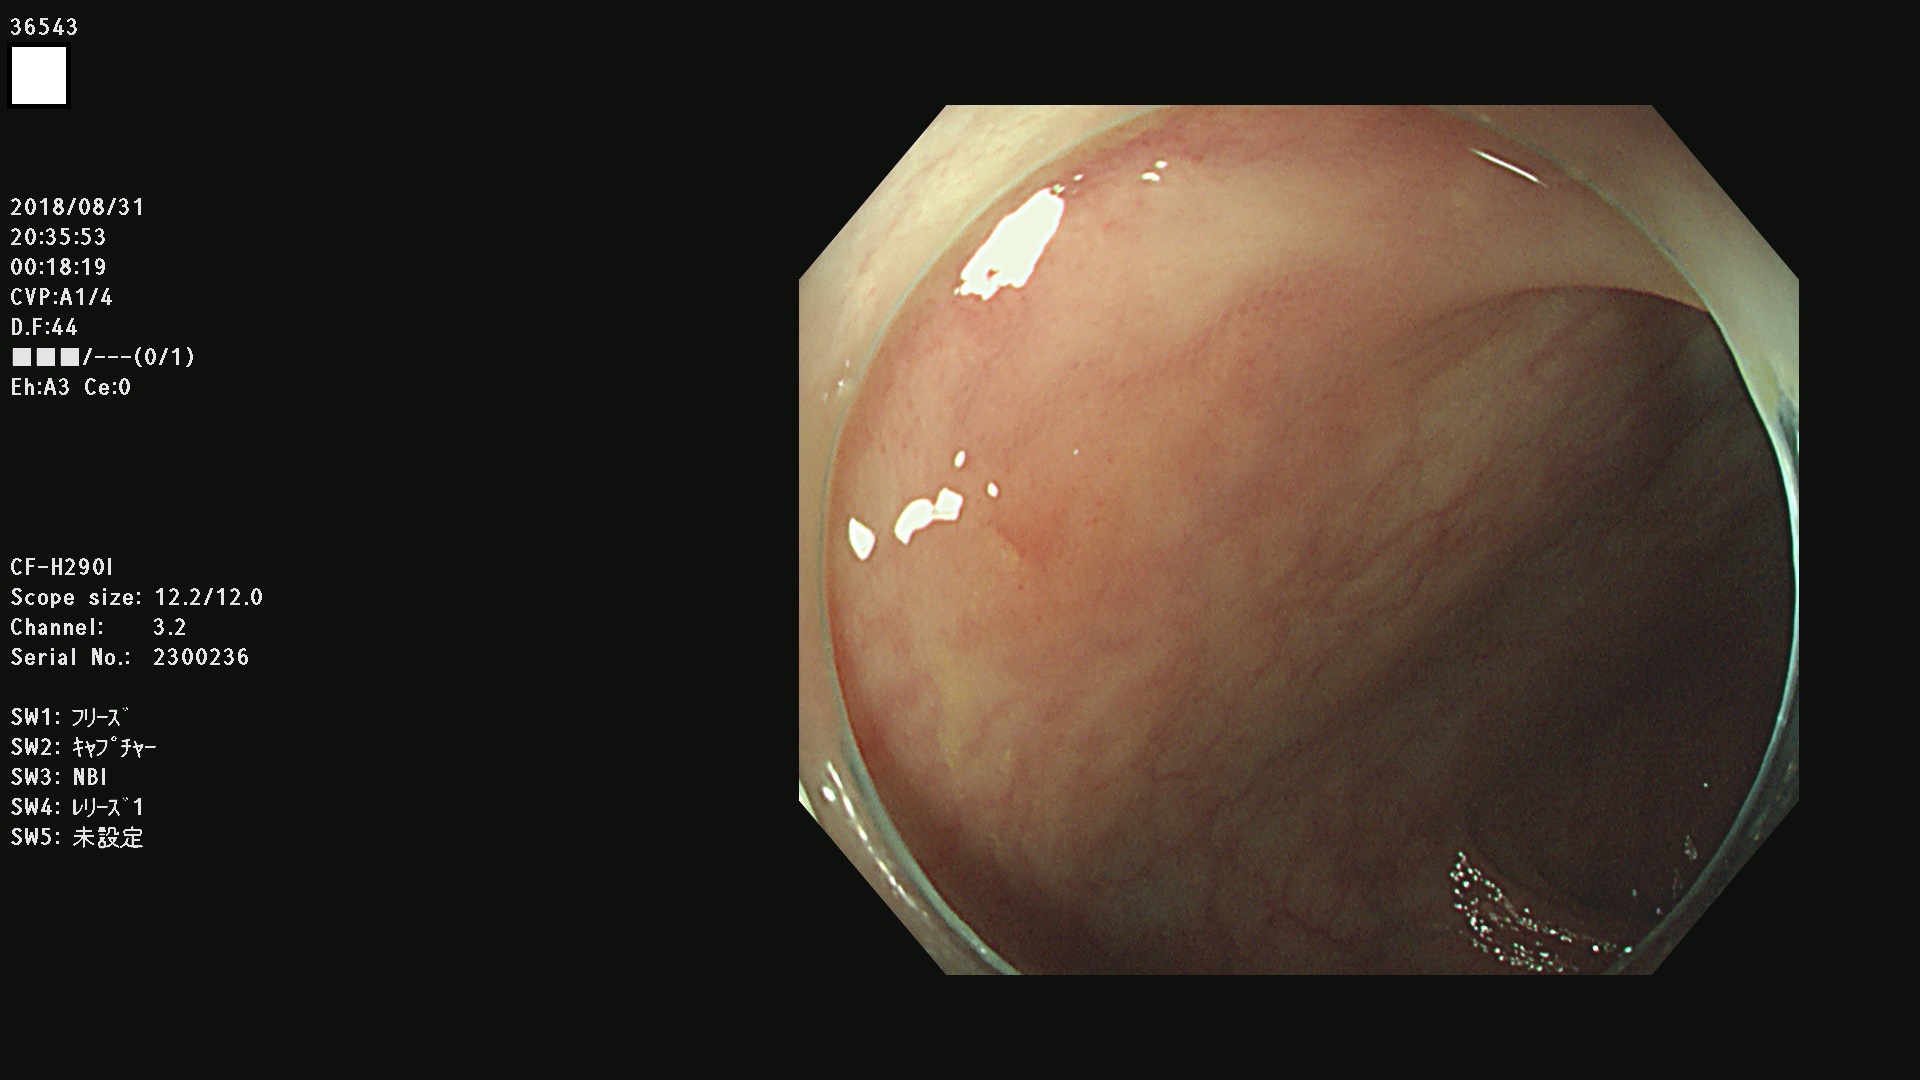

36500 36503 36504 36505 36507(SSAPのみ) 36508 36509 36510 36511 36514 36515 36517 36518 36520 36522(SSAPのみ) 36523 36524 36526 36528 36530 36531 36532 36533 36534 36535 36536 36538 36541 36542 36543 36544 36545 36546 36548 36550 36551 36554 36555 36556 36558 36559 36560 36561 36564 36565 36567 36568 36570 36572 36573 36574 36575 36576 36577 36578 36579 36580 36582 36584 36586 36591 36592 36593 36594 36595 36596 36597 36598

発見困難で危険性の高い平坦型病変(上記100名より抽出)